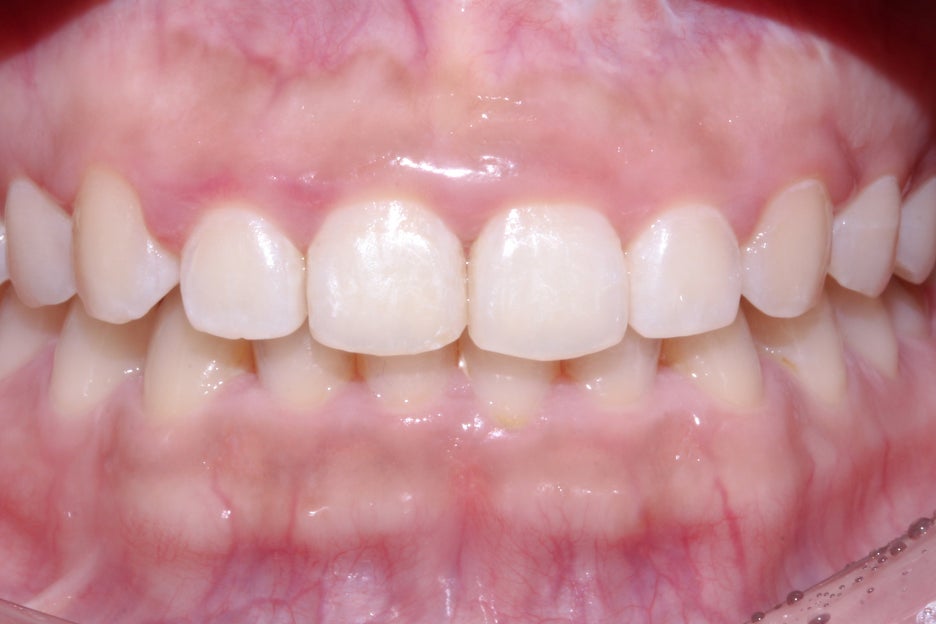

세라믹교정 종료 후 스마일라인의 모습입니다.

노출되는 상악 전치부 치아들이 교정 전보다

한결 가지런해진 모습으로 회전되었던

중절치의 변화가 특히 극적인 모습인데요,

전치부의 측면 사진에서도 나비치아 증상이

사리지고 바른 각도록 교정된 중절치를 확인할 수 있습니다.

구내사진을 보시면 브라켓을 부착했던 치아들이

모두 고르게 배열된 모습인데요, 부분교정의 경우

일반적인 전체교정보다 치아의 변위가 크지 않고

공간을 닫거나 여는 폭도 좁기 때문에

교정 전과 후의 차이가 명확하지 않을 수 있습니다.

옥니교정 후 중절치의 치축이 바르게 교정된 모습으로

세라믹 부분교정을 진행했던 상악 전치부 6개의 치아들이

모두 가지런해진 것을 확인할 수 있는데요,

교정이 종료된 후에도 유지장치를 반드시 착용하여

치아가 원래의 상태로 돌아가려는 힘을 막는 것이 중요합니다.